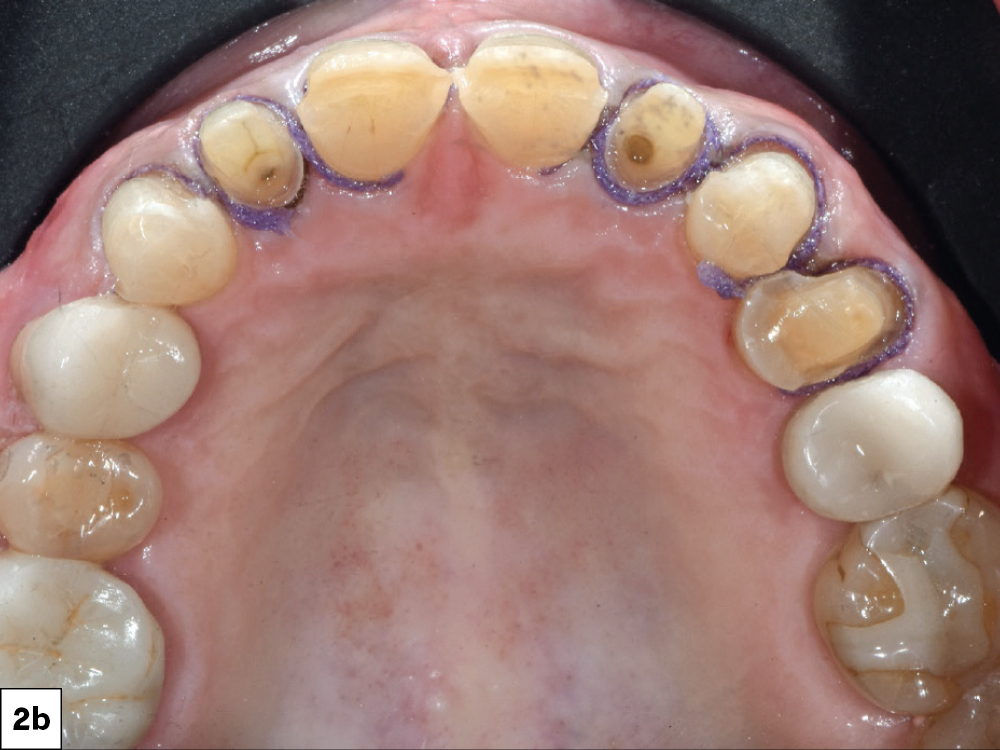

Figures 1a, 1b: The patient presented with failing Class V restorations, cervical wear, discoloration and chipping of the incisal edges.

Preparations were completed for teeth #6–12

A gingivectomy was performed on teeth #8 & #9

Figures 2a, 2b: A gingivectomy was performed on teeth #8 & #9 to create longer central incisors, as the gingival levels of the laterals were initially slightly higher than the centrals. Preparations were completed for teeth #6–12, and double retraction cords (00 and 0) were placed into the sulcus for optimal margin capture. The digital impression was taken with the iTero Element® 5D Plus intraoral scanner. I determined that a combination of crowns, veneers and an onlay would serve as the definitive treatment plan.